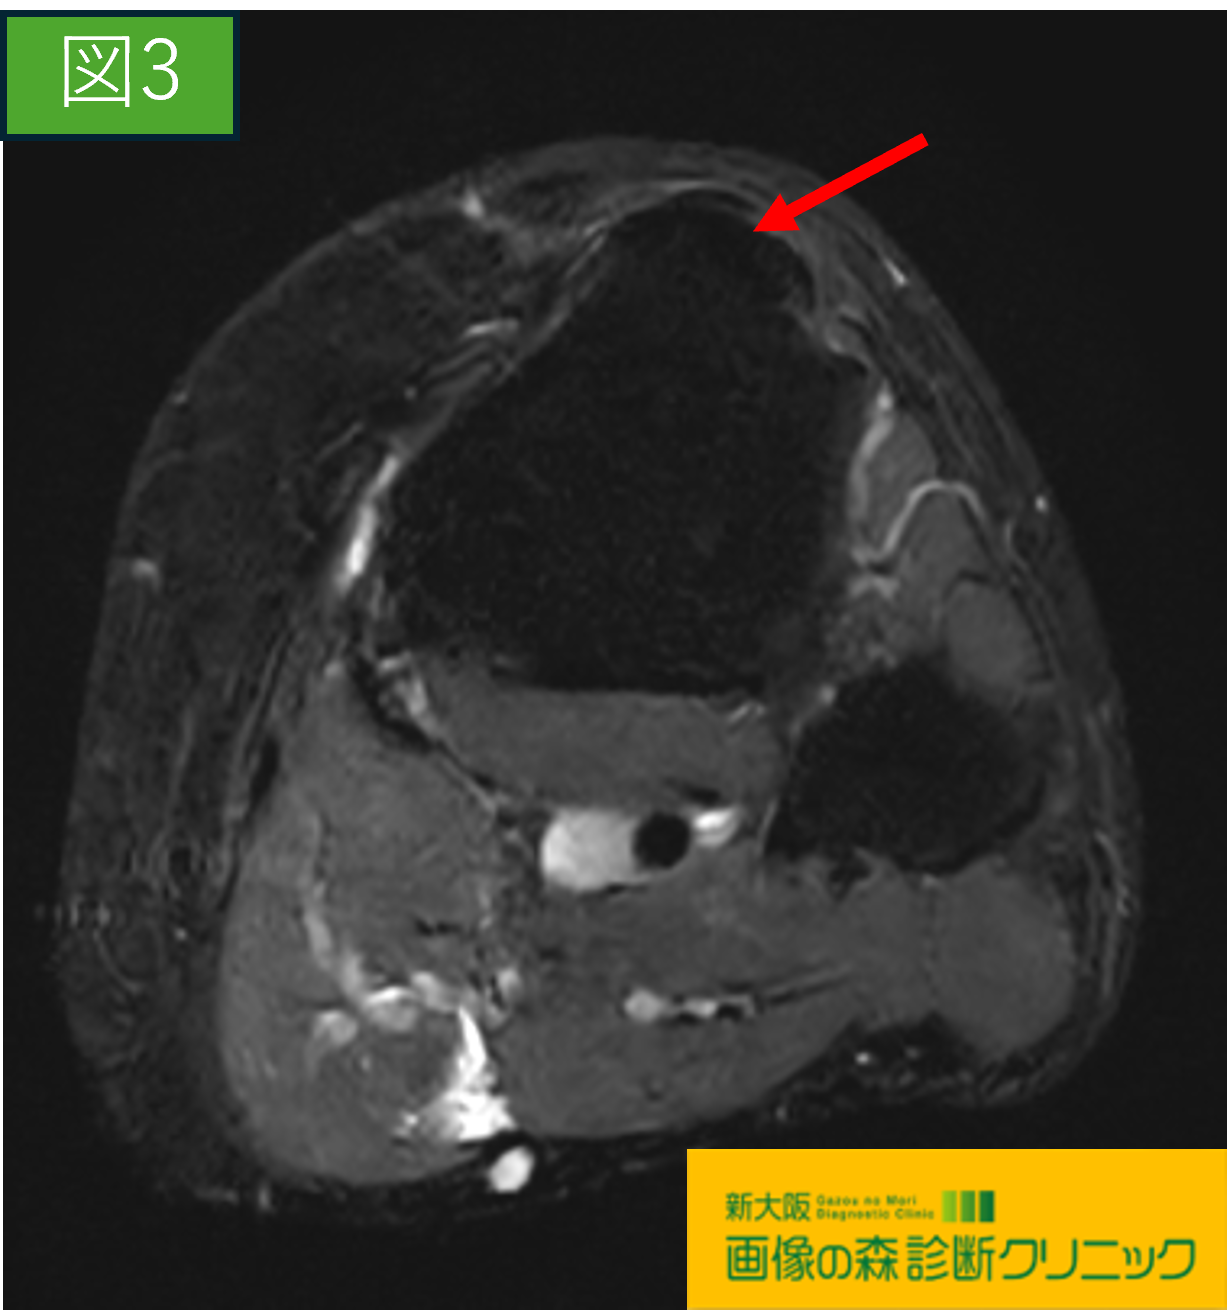

画像から図1・図3は正常膝関節の画像です。

図2・図4ではOsgood-Schlatter病の症例を示しています。

〇続けて図3・図4の画像は膝関節を輪切りで観察しています。

図3は正常画像

図4の赤矢印には、脛骨粗面(膝蓋骨のすぐ下)に

横方向に明瞭な亀裂が認められます。